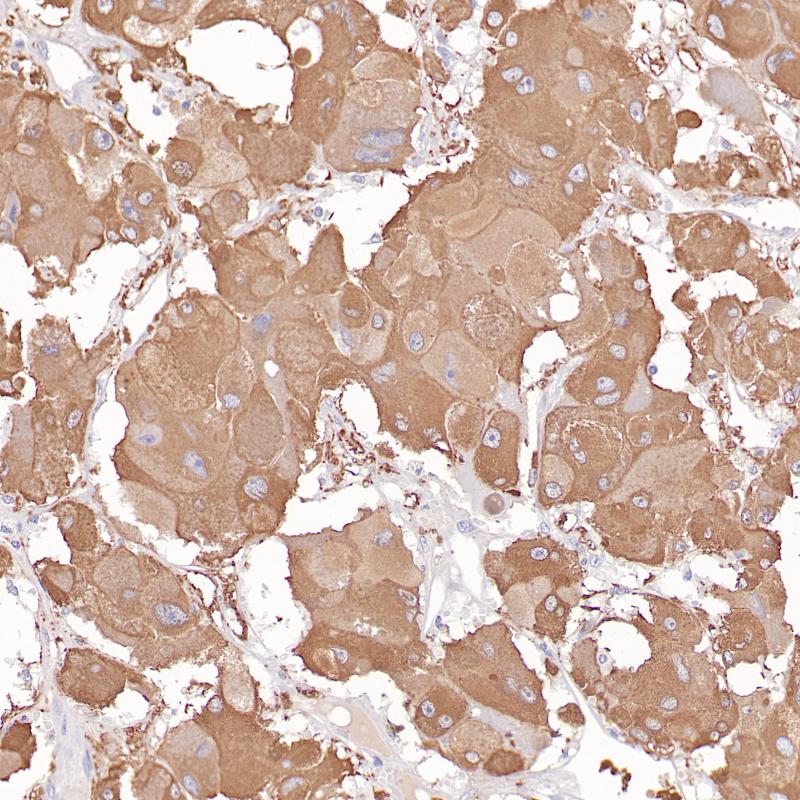

p40是p63蛋白的亚型之一,通常表达于复层上皮组织的基底细胞层或祖细胞层(如鳞状上皮、尿路上皮、支气管上皮)、某些腺上皮的基底细胞(如前列腺)、乳腺和唾液腺的肌上皮细胞、滋养层及胸腺上皮细胞。肿瘤组织中,p40在鳞状细胞癌中具有特异性表达,但肺腺癌中罕见表达,其对于肺鳞癌的敏感性类似于p63,但专一性明显优于p63,可用于肺鳞癌和肺腺癌的鉴别诊断。

阳性对照

前列腺

亚细胞定位

细胞核